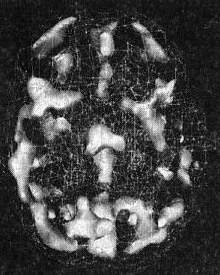

Познакомившись с Джеком, я увидел, что под озлобленной внешностью скрывается добрый мальчик. Томография ОЭКТ показала значительно повышенную активность по всему мозгу (рис. 8.1 и 8.2).

Мозг Джека

Рис. 8.1 До лечения

Повышенная в целом активность («кольцо огня»)

Мы называем рисунок таких снимков «кольцом огня». Снимок привлек внимание Джека, и он впервые заинтересовался своим лечением, стал задавать вопросы о томограмме и о своем мозге. На этой волне интереса он согласился принимать пищевые добавки и рыбий жир, стал работать со мной, чтобы научиться контролировать свой характер и лучше вести себя дома и в школе. Через четыре месяца после начала лечения мы заказали повторный скан. Его мозг, как и было ясно по его новому доброжелательному поведению, значительно успокоился. Сбалансировав мозг Джека, мы смогли изменить его жизнь.